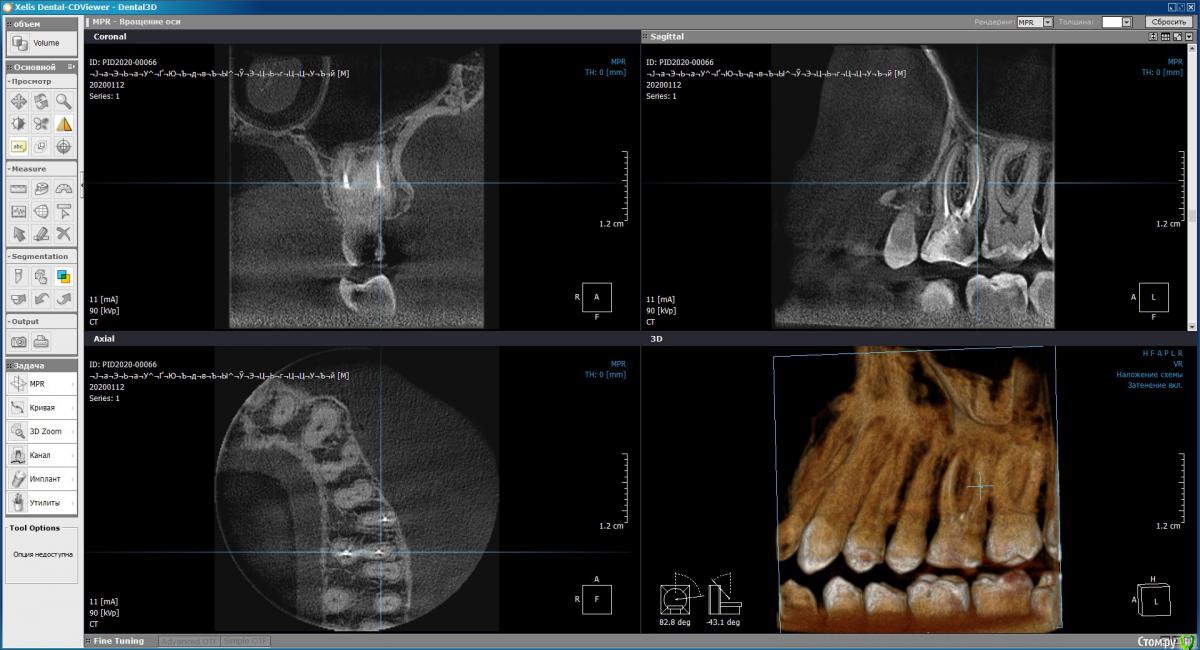

Demon_L Опубликовано 23 января, 2020 Поделиться Опубликовано 23 января, 2020 (изменено) Мне 36 лет, примерно 12 лет назад залечивал зуб (верхняя левая 6-ка), запломбировали 3 канала гуттаперчей, поставили обширную световую пломбу в хорошей платной клинике.Позже я стал замечать, что зуб немного темнее остальных, но не придавал этому значения, т.к. зуб не беспокоил. На днях откололся небольшой кусочек от этого зуба, пошел в клинику, сделали снимок КТ, сняли пломбу. Вердикт - 3 канала не требуют перелечивания, но есть 4-й канал, который требует лечения и который не нашли первый раз. Но что самое печальное - обнаружили перфорацию дна полости, которую по ошибке сделали при первом лечении, видимо когда искали 4-й канал. Тогда же видимо и положили раствор резорцин-формалина, что и придало темный с отттенками красного цвет зубу.Пока не нашли перфорацию, по снимкам склонялись к установке коронки, но после того, как обнаружили, один врач настойчиво рекомендовал удаление и имплантат, другой допускает коронку, но тоже рекомендует имплантат.Хотел бы спросить Вашего мнения, действительно ли при наличии перфорации дна полости (она небольшая, но файл в неё проходит и выступает капелька крови) ставить коронку противопоказано?Можно ли сначала залечить перфорацию, а потом ставить коронку? Прибегать к удалению и имплантации хотелось бы в последнюю очередь.Прилагаю несколько снимков КТ. Если они недостаточно информативны, готов выложить с любого другого ракурса. Могу вообще поделиться isо-файлом со снимком (образ CD), тогда можно будет покрутить в 3D как угодно у себя на ПК (запускается автоматически без установки чего-либо).Заранее спасибо за консультацию. Изменено 23 января, 2020 пользователем Demon_L Ссылка на комментарий

Дмитрий Л. Опубликовано 29 января, 2020 Поделиться Опубликовано 29 января, 2020 (изменено) Не соглашусь категорично. По кт там даже четвертый канал искать не надо. У вас 12 лет пролеченный зуб без проблем стоит. Темный цвет и скол решается коронкой.Риск трещины зуба есть. Этого зуба и любых других. Все удалить?Непонятно зачем перфорацию заново раскрыли. Идите в другую клинику, просите закрыть перфорацию и ставьте новую пломбу. Или коронку*Это вывод из ваших слов и приложенных срезов. Изменено 29 января, 2020 пользователем Дмитрий Л. Ссылка на комментарий